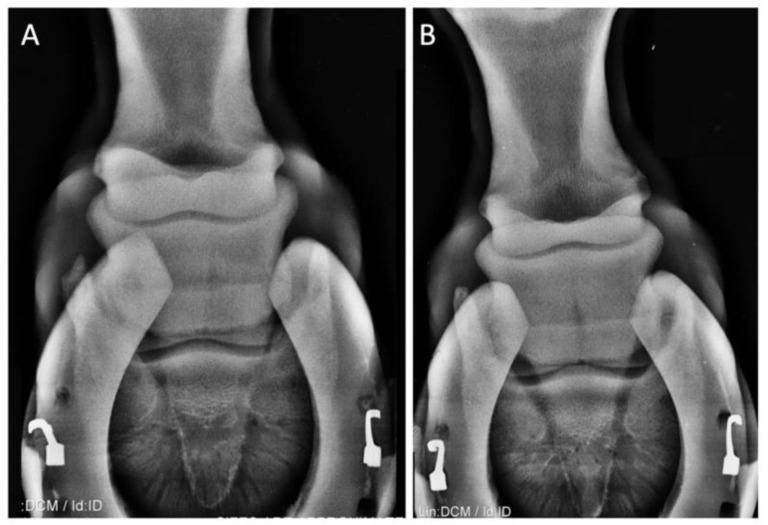

Lameness case study picture This picture demonstrates lameness case study.

Lameness examination found this horse to be sound at a walk, trot, and following upper limb flexion. Despite a normal physical exam, radiographs of both stifle joints identified abnormal flattening of the cartilage surface and the presence of bilateral sub-chondral bone cysts within both medial femoral condyles.